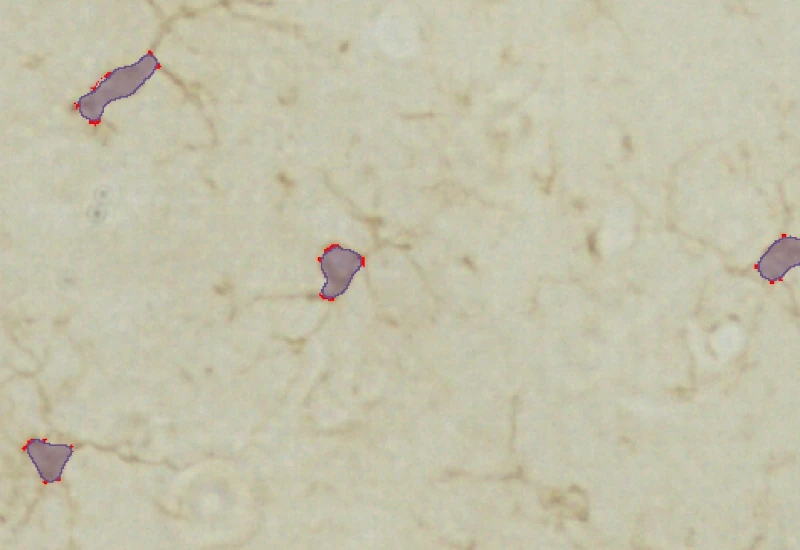

Soma detection

primary branch point detection